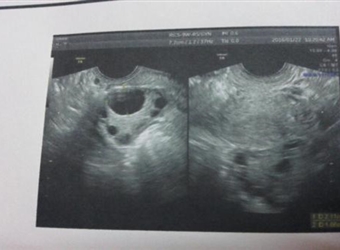

有的女性习惯于用排卵试纸来监测自己的排卵情况,也有的女性直接去医院做卵泡监测,那么,关于卵泡监测的事情大家了解多少,比如:卵泡监测什么时候做,卵泡监…

卵泡,是女性身体健康与否的重要组成部分,它也是女性能否顺利受孕的必备条件。现实生活中有一些女性她们不容易受孕成功,往往跟卵泡有很大关系,然而,卵泡之…

女人怀孕不是一件容易的事情,讲究的是天时、地利、人和,虽然,现实生活中有少部分女性很容易怀孕,她几乎是碰不得一碰就中招,女人每个月都会排卵,优势卵泡…